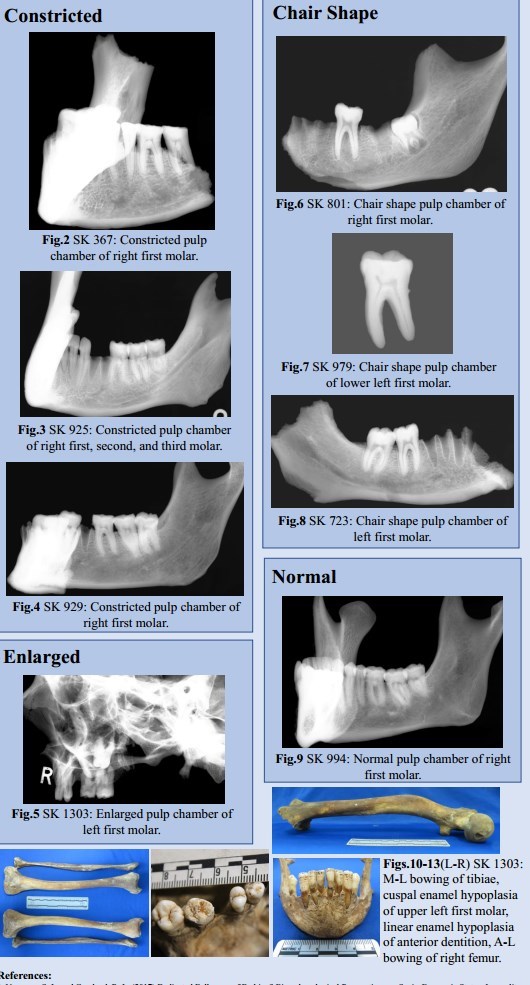

30 adult individuals had suitable teeth and were selected for radiography (Nmale=17, Nfemale=13). All teeth were radiographed at the University of Bradford’s radiography laboratory using a Faxitron Cabinet X-ray System. The specimens were orientated as if a bitewing dental radiograph was being taken, from a lingual to buccal view in order to show the pulp chambers. All specimens were radiographed between 50-60kV for 90 seconds. The method established by D’Ortenzio et al. (2018) was followed to identify morphological changes in the pulp chamber (Fig.1).

Fig. 1: Diagram of different pulp chamber shapes in a generic permanent molar. Source: D’Ortenzio et al. 2018:4

However, 28 individuals exhibited evidence for constricted (N=16) or chair-shaped (N=12) pulp chambers associated with vitamin D deficiency during pulp chamber formation.

One adult male aged 18-25 years exhibited a normal pulp chamber.

One further adult male aged 26-35 years exhibited an enlarged pulp chamber. This molar has an abnormal, poorly mineralised occlusal surface consistent with cuspal enamel hypoplasia (CEH) (Fig. 11).

Of the 30 individuals analysed, 28 exhibit morphological changes to the pulp chamber consistent with vitamin D deficiency. Deficiency must occur during pulp chamber formation for morphological changes to arise (1.5-2 years in males, and 1.4-2 years in females), therefore these results suggest that the vast majority of adults in this sample group experienced prolonged vitamin D deficiency ~1.5 years of age.

Two individuals exhibit change in the first, second, and third molars, indicating chronic or recurring deficiency throughout childhood. Neither exhibited skeletal evidence for vitamin D deficiency.

SK1303 exhibited an enlarged pulp chamber. Clinically, this has been linked to both vitamin D- resistant hypophosphatemic rickets and odontogenesis imperfecta.6 This individual is currently the subject of further research, as they also exhibit skeletal change consistent with residual rickets (See Figs.10-13).